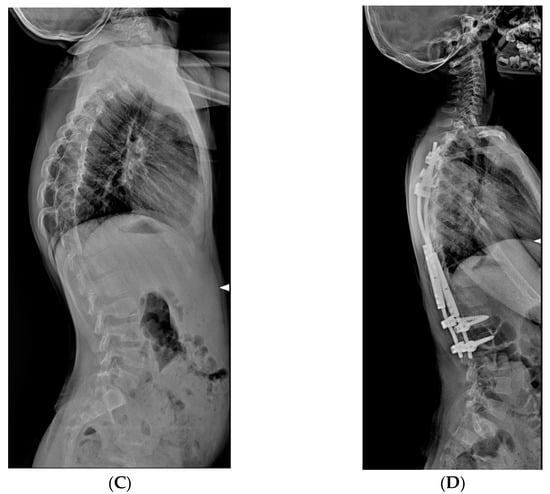

2.3.3. VEPTR: Vertical Expandable Prosthetic Titanium Rib

3.2. Curve Correction